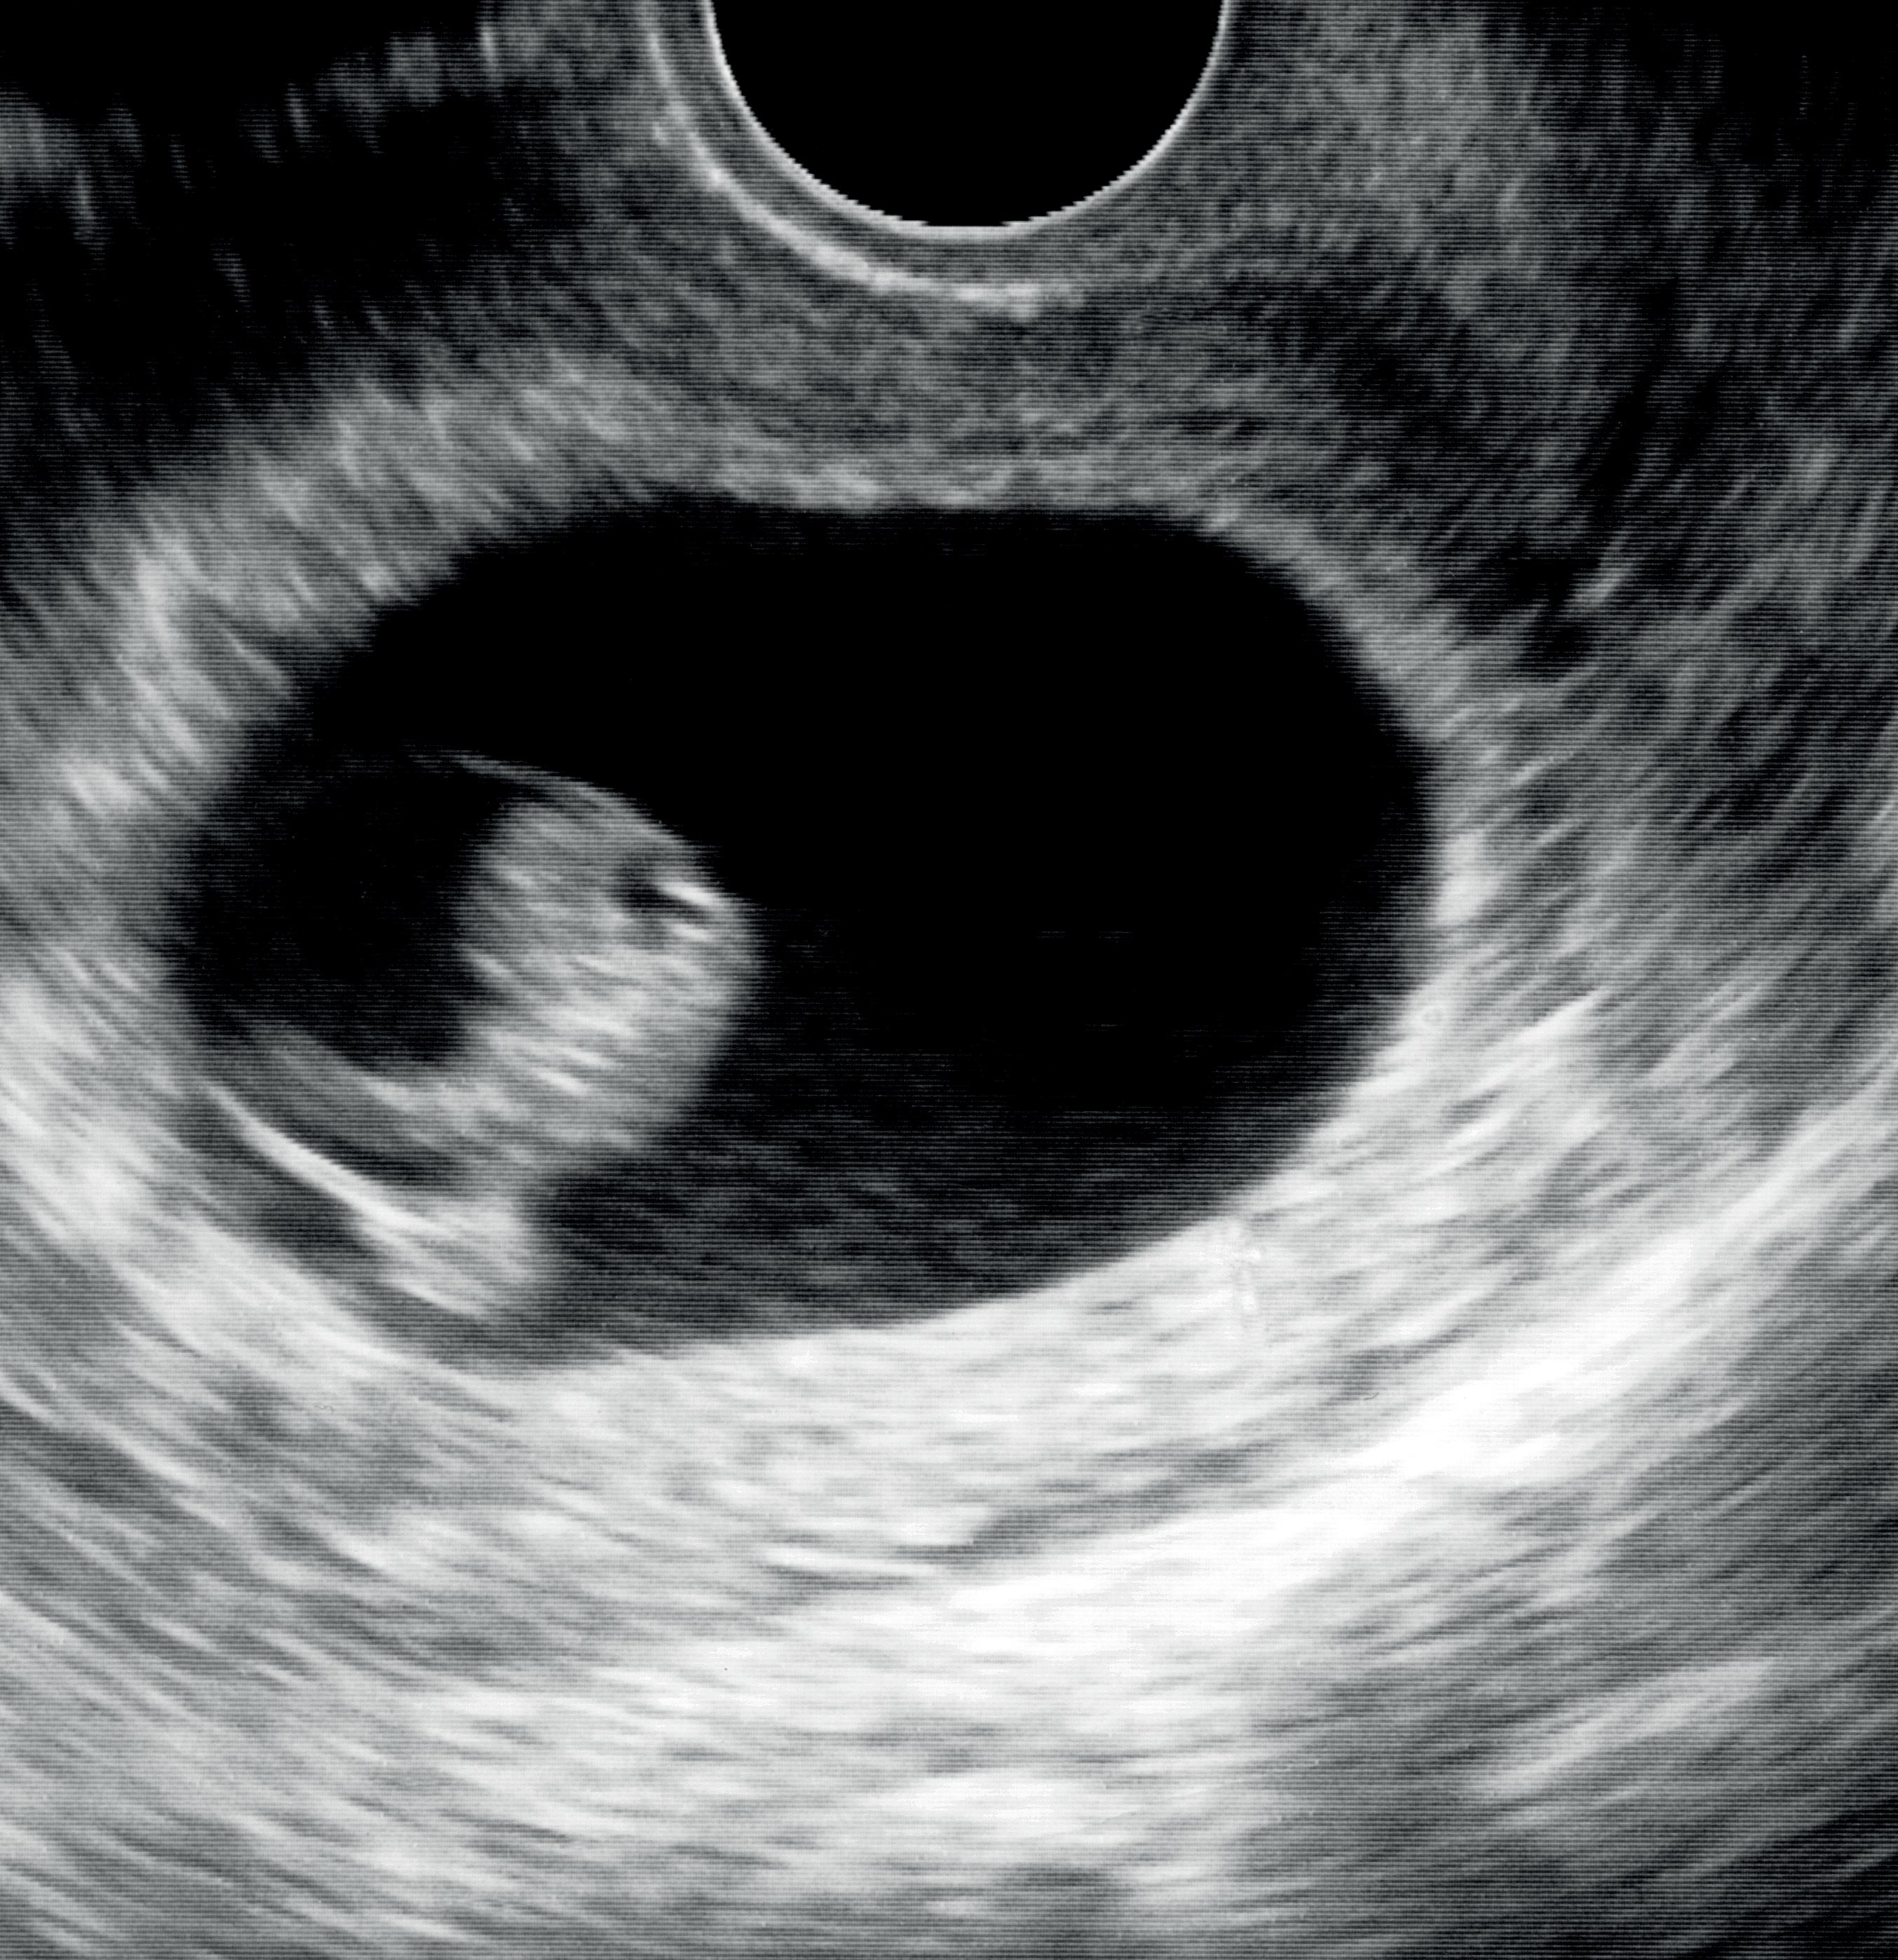

Så kom A-ha-opplevelsene, jeg husker ikke hva min første var, fordi det ble så mange. Kanskje det var å oppdage en veldig tidlig intrauterin graviditet og være trygg på det. Nei, ikke en gestasjonssekk på en centimeter, men bare på noen millimeter. Eller å finne den tubargraviditeten på tre millimeter i pasientens høyre tube. Ser man dem så tidlig, forstår man at svært mange ikke trenger operasjon, men kan behandles med ekspektans. Jeg begynte å forstå arrgraviditeter. Det tok meg hele året, og jeg tror ikke at jeg egentlig hadde noe begrep om det før. Det var gøy å være med å se veldig sjeldne ektopiske graviditeter og hvordan de ble håndtert.

Kurset dekket et bredt spekter av temaer innenfor tidlig svangerskap. Et foredrag som ble veldig godt mottatt var Jackie Ross foredrag om identifisering av tubare ektopiske svangerskap med ultralyd. Flere videoer viste oss nøyaktig hvordan man følger tubene fra interstitium frem til fimbria, både når tubene inneholder et svangerskap og for normale tuber. Dr. Ross viste også eksempler på hvordan endometrium kan se ut ved ektopiske svangerskap, samt tips for å finne et tubart svangerskap.